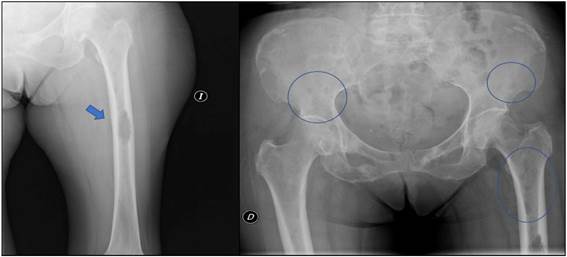

Se realizó una radiografía del miembro inferior izquierdo que mostró una lesión osteolítica de 51 por 22 mm en el tercio medio del fémur, de bordes irregulares y que destruía la cortical (Figura 1A). En el tercio superior y la pelvis se observaban otras lesiones osteolíticas de menor tamaño (Figura 1B). La radiografía de tórax mostraba una cardiomegalia con ensanchamiento mediastínico y redistribución vascular (Figura 2A). En la analítica se objetivó una anemia con hemoglobina de 8,1 g/dl, aumento de proteínas 11,1 g/dl, LDH 1212 UI y calcio 10,4 mg/dl. Además, presentaba un deterioro de la función renal, con una creatinina de 1,52 mg/dl y un filtrado glomerular de 31 ml/min/1,73m2. Se decidió ingreso hospitalario para completar estudio.

El rol de las imágenes en el MM incluye la evaluación de la extensión de la enfermedad, la identificación y caracterización de las complicaciones como fracturas patológicas o compromiso neurológico1. La radiología convencional sigue siendo el método estándar para evaluar el compromiso óseo, aunque solo permite la identificación de lesiones con destrucción avanzada con un mínimo de afectación del 30 % del hueso trabecular1,3. La radiografía es anormal en el 79 % de los pacientes en el momento del diagnóstico, el 67 % de los casos presentan lesiones líticas y el 20 % tienen osteoporosis, fracturas patológicas o fracturas vertebrales1. Las lesiones radiográficas típicas son líticas y en “sacabocados”. En los huesos planos, como los del cráneo y pelvis, no suele haber esclerosis reactiva en el hueso circundante3. En el caso de los huesos largos, las lesiones pueden manifestarse como festoneado endóstico, lesiones líticas o áreas moteadas por la conjunción de múltiples lesiones pequeñas (Figura 1B), hasta grandes lesiones destructivas3) (Figura 1A). Estas lesiones osteolíticas presentan un tamaño uniforme y unos márgenes bien definidos, siempre son subcorticales y elípticas, y son capaces de coalescer en grandes segmentos de destrucción. Un rasgo característico es una radiolucencia circular de localización subcortical asociada a erosión de los bordes internos corticales3. Hasta el 84 % desarrollarán lesiones esqueléticas en algún momento durante el curso de la enfermedad1. También puede manifestarse como una osteopenia difusa sin lesiones líticas, principalmente a nivel de la columna vertebral. Esta situación facilita la presentación de fracturas por compresión. La tomografía computarizada tiene mayor sensibilidad que la radiografía convencional para detectar lesiones líticas pequeñas1,3. Además, ayuda a planificar la radioterapia y un eventual procedimiento quirúrgico. La resonancia magnética es la técnica de elección para la evaluación de la columna vertebral en pacientes con MM asintomáticos o con clínica de compresión medular o radicular1. Tiene una sensibilidad del 92 % para la detección de lesiones líticas en columna lumbosacra, siendo superior a cualquier otro método de imágenes1. La tomografía de emisión de positrones es una imagen de tomografía nuclear que utiliza radiofármacos marcados como la fluorodesoxiglucosa (FDG) que identifica a las células tumorales debido a su elevada tasa metabólica y alta demanda de glucosa3. Posee una sensibilidad del 72 % para detectar compromiso óseo, aunque es menos eficiente para identificar lesiones en el cráneo, debido a la alta captación fisiológica del trazador en el cerebro adyacente1. Su principal ventaja es la capacidad de distinguir entre mieloma activo (FDG positivo) y la gammapatía monoclonal de significado inespecífico o enfermedad latente. Finalmente, tanto la densitometría ósea como la gammagrafía con tecnecio no son recomendadas en la evaluación del MM1,3.